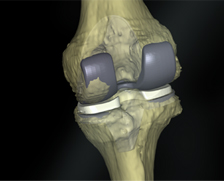

• 사전 인공관절 선택과 정확한 인공관절 삽입

정확한 수술계획만큼 중요한 것은 인공관절의 선택과 삽입입니다.

의사는 로봇을 이용해 환자의 관절에 맞는 인공관절을 선택하고 정확하게 삽입합니다.

• 서브 밀리미터 치수 정확도와 우수한 정렬을 위한 정밀한 커팅

정확한 뼈 절삭은 우수한 결과를 제공합니다.

큐렉소의 인공관절 수술로봇은 서브 밀리미터 수치의 정확도와 정밀한 절삭으로 환자 다리축의 바른 정렬을 불러와 우수한 수술결과를 보여줍니다.